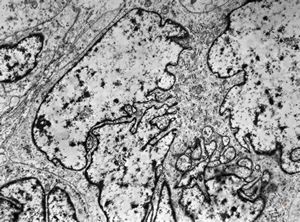

F,25y. | myopathy - atrophic and regenerating muscle cells

M,2y. | myopathy - regenerating muscle cell